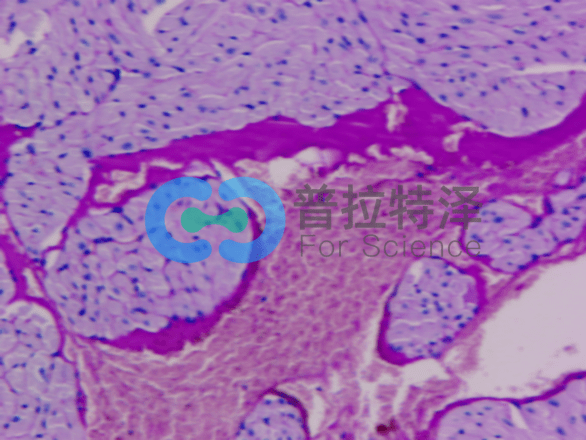

首先,我們來(lái)了解PAS染色的基本原理。它利用過(guò)碘酸將細(xì)胞中的多糖類(lèi)物質(zhì)氧化,再通過(guò)雪夫試劑與氧化后的多糖結(jié)合,形成特征性的紅色或紫色沉淀。這種沉淀能夠清晰地顯示出細(xì)胞中的多糖類(lèi)物質(zhì)分布和含量,從而幫助我們了解細(xì)胞的代謝狀態(tài)和功能特點(diǎn)。

在PAS染色實(shí)驗(yàn)的第一個(gè)層次,我們需要關(guān)注實(shí)驗(yàn)步驟和操作要點(diǎn)。實(shí)驗(yàn)過(guò)程中,首先需要對(duì)樣本進(jìn)行固定和脫水處理,以確保細(xì)胞的形態(tài)和結(jié)構(gòu)不受破壞。然后,利用過(guò)碘酸對(duì)細(xì)胞進(jìn)行氧化處理,使多糖類(lèi)物質(zhì)發(fā)生特定的化學(xué)變化。接著,通過(guò)雪夫試劑與氧化后的多糖結(jié)合,形成可見(jiàn)的沉淀。最后,通過(guò)顯微鏡觀察樣本的染色情況,分析細(xì)胞中的多糖類(lèi)物質(zhì)分布和含量。